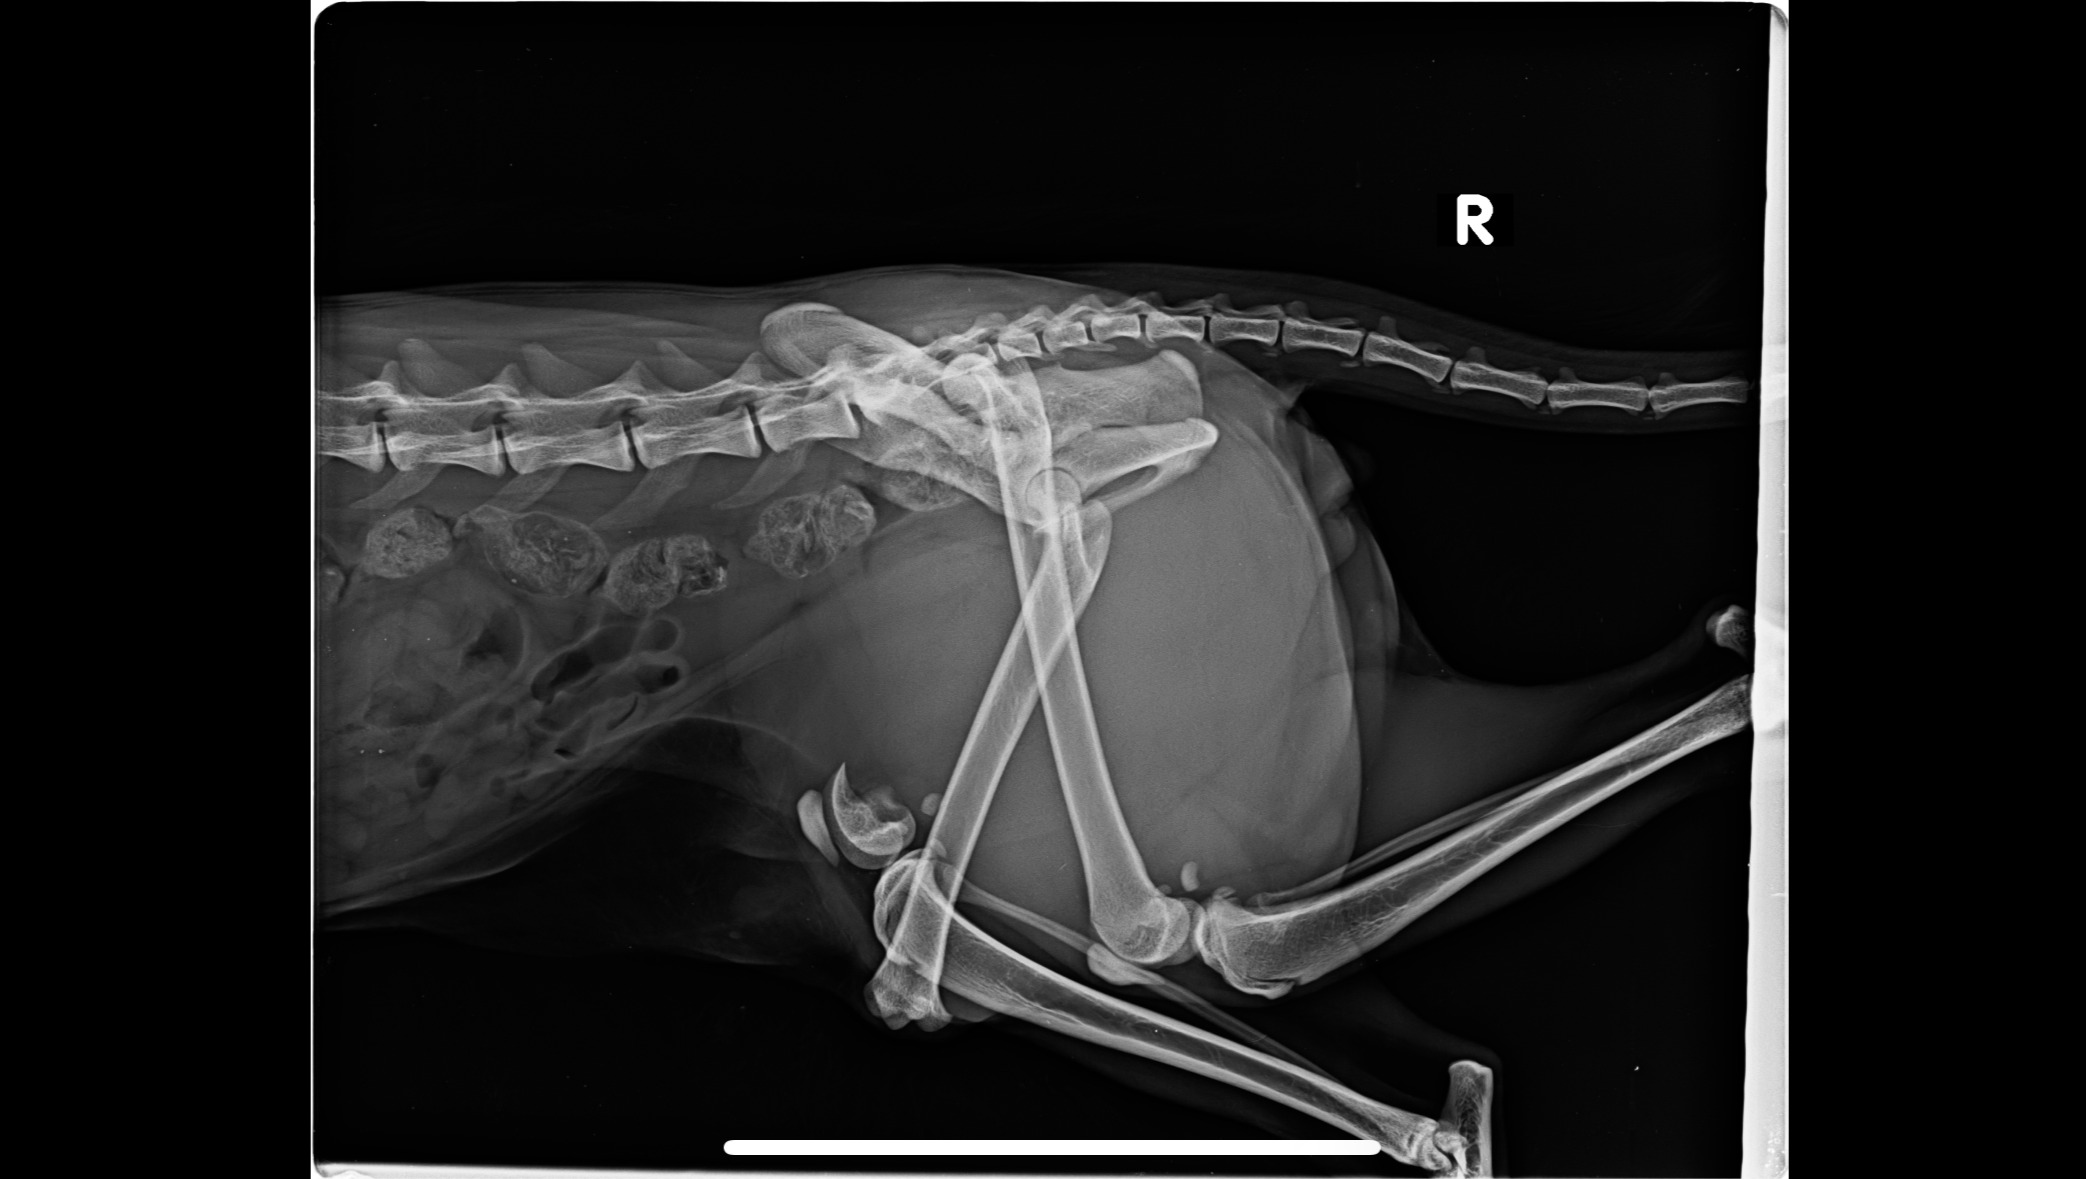

Die Diagnose der Tierklinik in Oberhaching war niederschmetternd:

• Rechtes Hinterbein: komplexe, comminutive Femurfraktur (mehrfragmentärer Bruch des Oberschenkels)

• Linkes Hinterbein: Luxatio coxae (Hüftluxation, also ein ausgerenktes Hüftgelenk)

Laut den Ärzten sind beide Befunde hoch komplex und schwierig zu lösen. Zum Glück ist Mochi in Oberhaching bei München in den besten Händen

• Nachsorge, Kontrolluntersuchungen & Röntgen